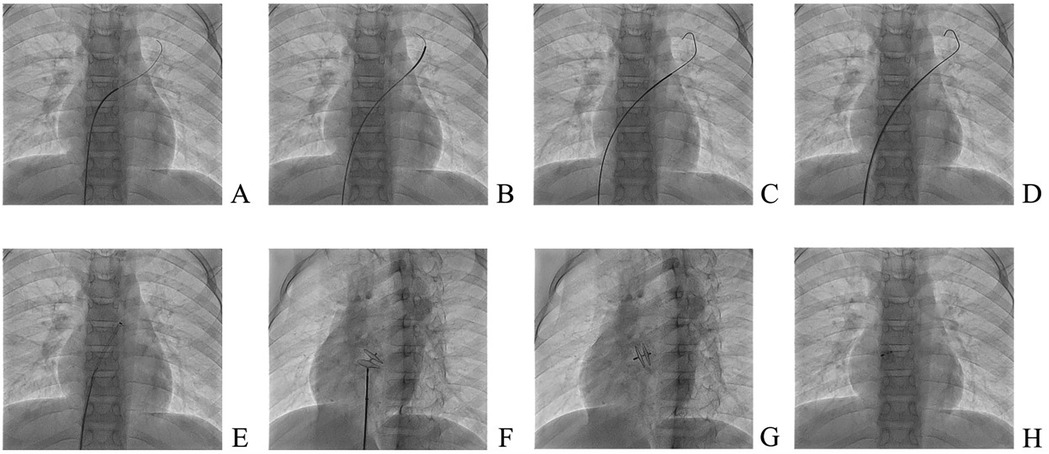

Patients underwent intervention under general anaesthesia and transesophageal ultrasound monitoring using an 18/18 mm PFO occluder (Huayi Shengjie Co., Ltd., Beijing, China). After general anaesthesia, patients were positioned supine, disinfected, and covered with a towel. The right femoral vein (RFV) was punctured, a 6 Fr vascular sheath was inserted, and a 5 Fr multifunctional catheter was inserted through the RFV to the fossa ovalis. A loach guidewire was inserted through the foramen ovale into the left upper pulmonary vein, and a multifunctional catheter was inserted along the loach guidewire into the left upper pulmonary vein. The loach guidewire was then pulled out, a 260 cm 0.035-in exchange guidewire was sent through a 5 Fr multifunctional catheter and fixed in the left upper pulmonary vein, and the 6 Fr delivery sheath was transported along the guide wire to the left upper pulmonary vein opening. The inner sheath and guidewire were then pulled out and the occluder was sent along the long sheath to the left atrium. The left atrial umbrella was released, the right atrial umbrella was released into the right atrium, and the atrial interval was fastened. Intraoperative oesophageal ultrasound was used to observe whether the occluder had any effect on the surrounding structures. If there was no effect, the occluder was released and local pressure was applied to stop bleeding. An 18/18 mm occluder was used in all operations. Dual antiplatelet therapy with aspirin (3–5 mg/kg/d, max 100 mg) and clopidogrel (1 mg/kg/d, max 75 mg) was administered post-intervention for three months, followed by aspirin monotherapy for an additional three months. All antiplatelet medications were discontinued after six months. The PFO occlusion procedure in illustrated in Figure 3. Ultrasound changes before and after intervention are reported in Figure 4.

Figure 4. Ultrasound changes before and after intervention. (A) Ultrasound before plugging; (B) Short axial section of the great artery after closure; (C) Four-chamber view of the heart apex after closure; (D) Double-compartment section below the xiphoid process after closure.